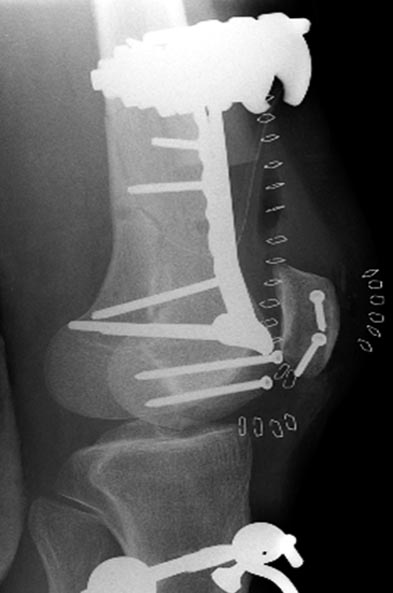

Раны в области коленного сустава и на плече до сих пор чистые, остаются

открытыми. Отсутствует признаки инфекции, решили превратить недостаток в

преимущество, т.е. фиксировать через открытые раны пластинами.

На 9й день фиксация дистального бедра, где фрагмент Hoffa и вертикальный

перелом надколенника, зафиксированы винтами.

На 11й день фиксация плеча также пластиной.